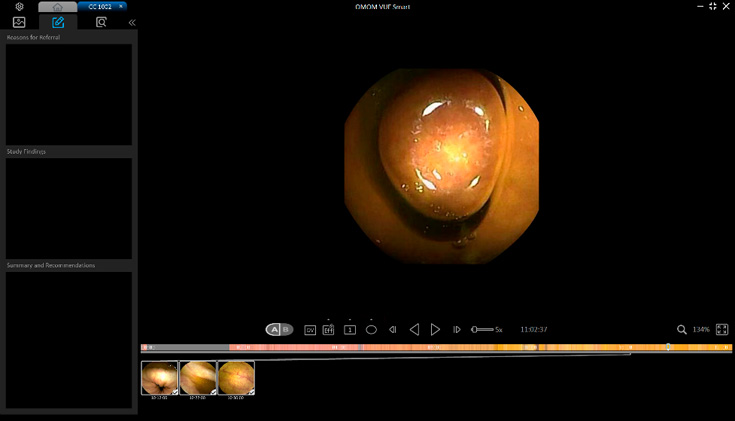

Vue Smart™

Wykorzystując zastrzeżone algorytmy sztucznej inteligencji, SmartScan przetwarza surowe pliki obrazów, usuwając do 90% nadmiarowości, identyfikując i oznaczając aż 16 rodzajów nieprawidłowości.

Tryb czytania SmartView odtwarza tylko obrazy pobrane przez Smartscan, pomagając nam szybciej poruszać się po całym filmie. Dzięki temu możemy przyspieszyć proces diagnostyczny.

Tryb czytania SmartView odtwarza tylko obrazy pobrane przez Smartscan, pomagając nam szybciej poruszać się po całym filmie. Dzięki temu możemy przyspieszyć proces diagnostyczny.